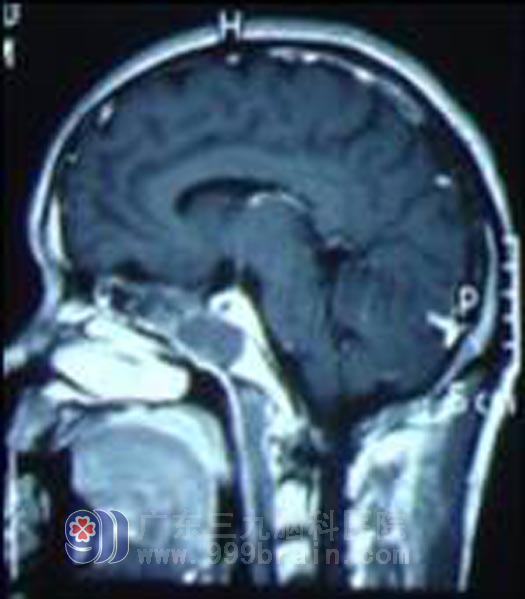

杨先生,37岁,广西容县人,半年前无诱因出现左眼视物模糊,当时以为是用眼过度,视力问题,就买了眼药水滴眼,也不见好转,而且视力越来越差,杨先生意识到肯定不是视力问题这么简单,就去了当地人民医院做了头颅CT,显示左侧筛窦及蝶窦团块状高密度应,累及左侧眼眶内侧壁、视神经,建议上级医院治疗。杨先生在网上查了能治疗这种病的医院,于4月份来到广东三九脑科医院就诊,我院头颅MR检查提示肿瘤为鼻咽起源。http://www.999brain.com/

查体:患者右眼睑下垂,右眼视力5.2,左眼睑下垂,左眼视力20cm为4.0,完善相关检查后,4月13日行鼻腔肿物活检术,病理结果回报示鼻咽癌T4N2M0A.5月3日-6月28日行适形调强放疗,完成74Gy,并同步完成6次化疗。放疗结束后再行辅助化疗,治疗后影像学检查见鼻咽癌基本消失。随访见其右眼视力5.2,左眼视力4.7,杨先生一般状态良好。http://www.999brain.com/

放疗前